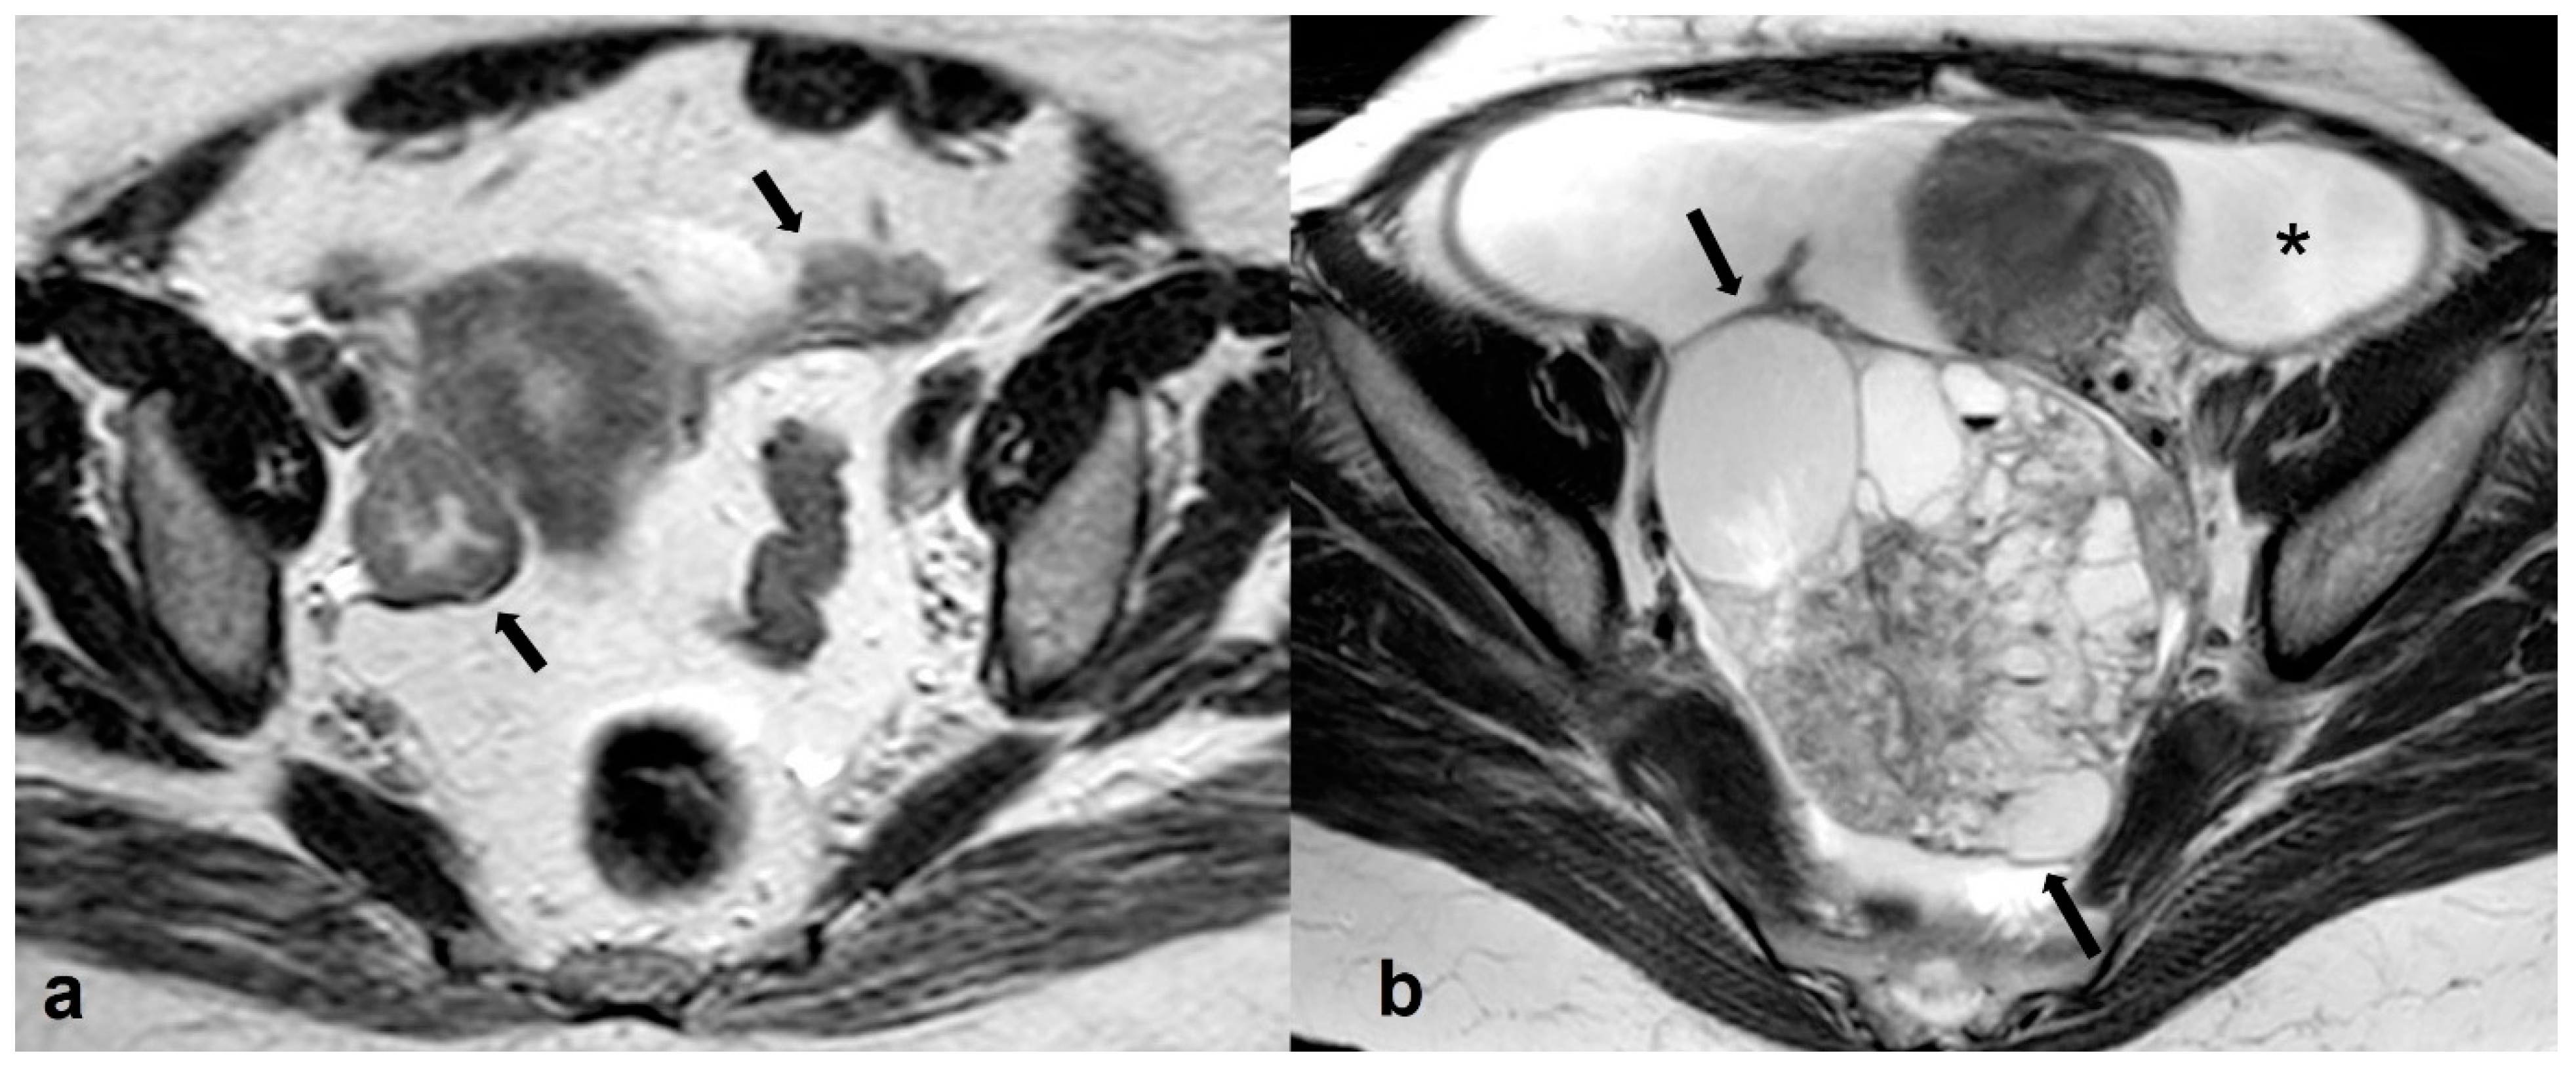

2.2.1. Cystadenofibroma

2.2.2. Fibrothecoma